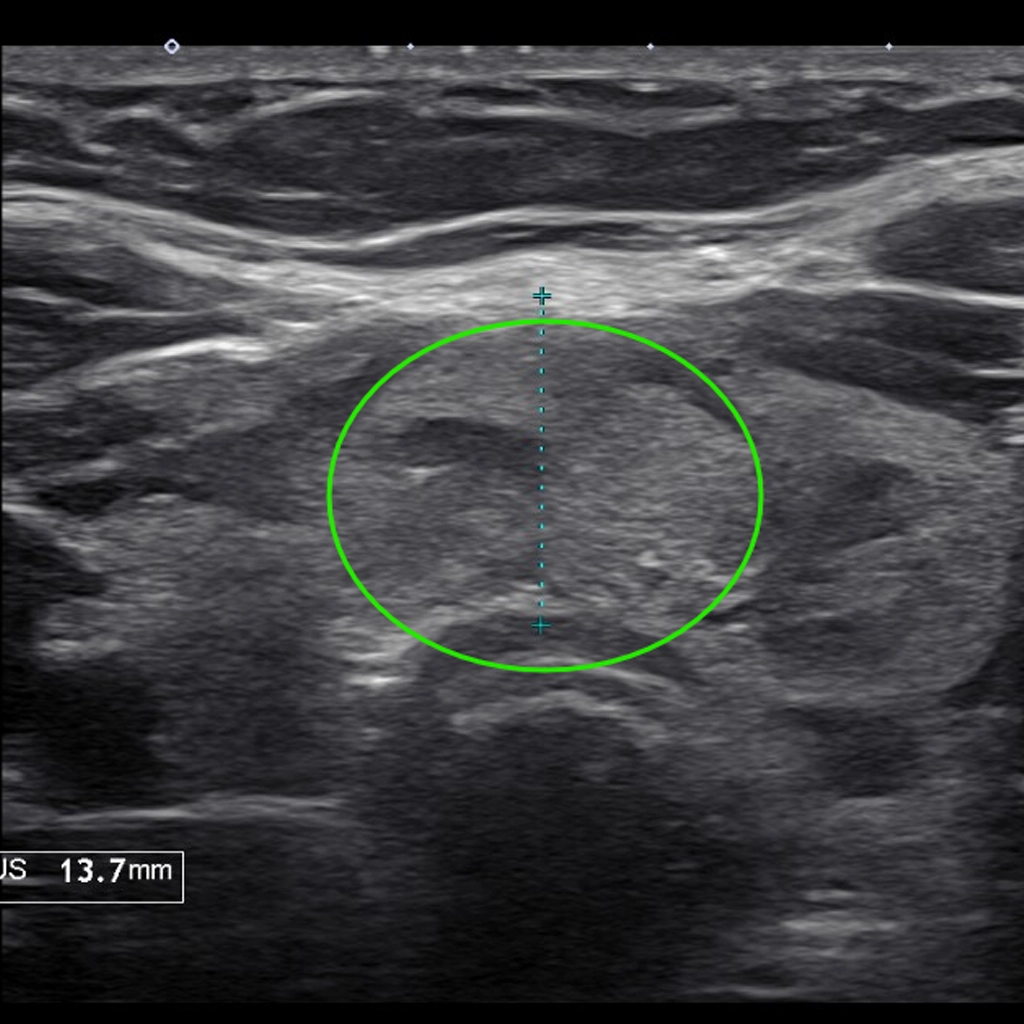

At 6 weeks, the nodule had shrunk ~70% to the size of a pea.

Natalie’s Story

Natalie, a lifelong singer, noticed she could no longer hit her high notes. She felt a thyroid lump pressing on her throat and voice box. An ultrasound confirmed an isthmus thyroid nodule the size of a small grape. The team at NSVI shrunk her thyroid through a minimally invasive procedure called Thyroid Radiofrequency Ablation. Within days, Natalie felt relief from her previous throat pressure. At 6 weeks, the nodule had shrunk 70% and down to the size of a pea. She could sing the high notes again! Plus, she had no scar and didn’t have to go through surgery.